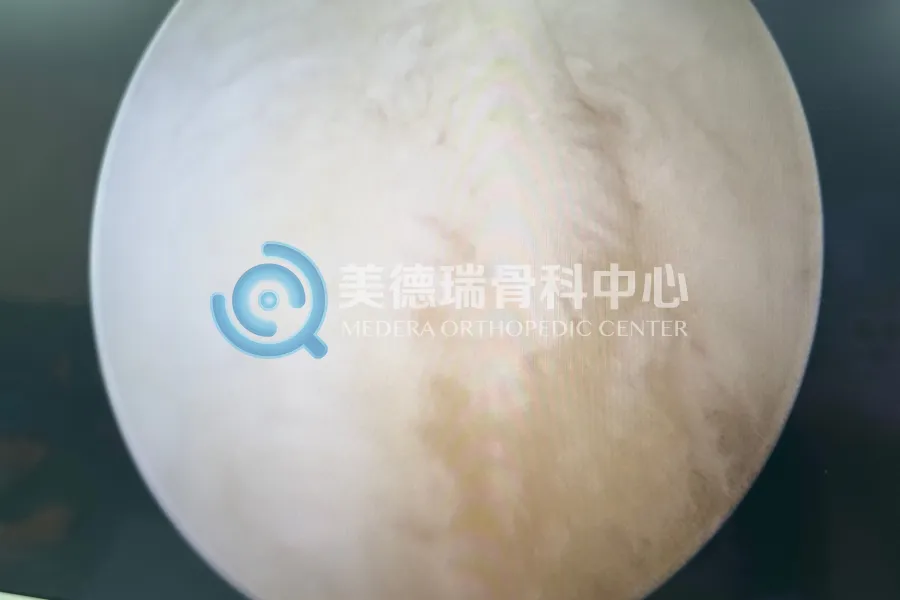

经过细致的查体与影像学评估,病因最终被锁定:一枚游离体卡在了髁间窝及后关节囊的深处,正是它构成了关节伸直的物理性阻挡。

依托美德瑞骨科医生集团成熟的微创技术体系,张威医生专家团队为患者实施了关节镜下经后内侧入路游离体取出术。这一术式避开了大面积切开,在保护周围血管神经的前提下,通过微创通道直达关节后室,精准移除了那枚长期卡压关节的游离体。

术后,随着关节内的机械性阻挡被解除,患者的膝关节伸直功能得到了显著改善。由于手术创伤较小,患者术后无需长时间卧床,在进行常规的康复指导后,便能逐步恢复正常的行走活动。